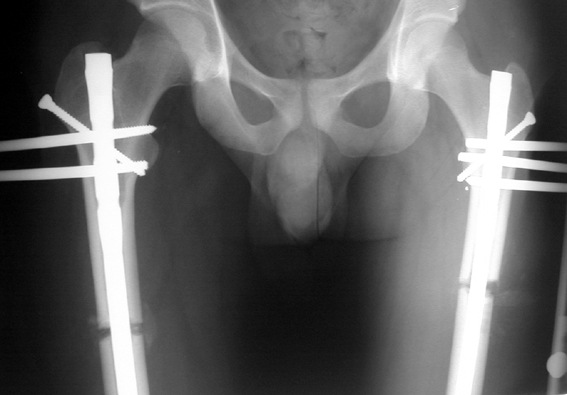

Eksternal fiksatör uygulanımı: İntramedüller çiviye değmeden aşağıya ve yukarıya üçer adet Schanz vidası gönderilir. Vidalarla çivi arasında en az 1 mm den fazla mesafe olmalıdır.

Biz son zamanlarda, seçilmiş vakalarda, uzatma sonrası uzunluğu ve “alignment’ı” korumak amacı ile unilateral dinamik aksiyel fiksatör ve kilitli intramedüller çivi kombinasyonunu tercih etmekteyiz. Bu yöntemin ön şartları medullanın en dar çapının 7 mm.’den geniş olması ve uzatma sonrası distalde en az 8 cm. uzunluğunda çivi kalabilmesidir. İntramedüller çivi hem uzatma esnasında femurun üzerine gelen makaslama ve bükülme kuvvetlerini nötralize etmekte hem eksternal fiksasyon süresini kısaltmakta, hem de yeni oluşan kemiği kırıklara karşı korumaktadır. Serimizde bir vakada subtrokanterik femoral osteotomi yapılmıştır. İntramedüller çiviye rağmen varus angulasyonu oluşması yönünde bir dezavantaj tespit etmedik.

İlizarov, distraksiyon osteogenezisi için endosteal kan dolaşımının önemini vurgulamıştır. Biz tüm vakalarımızda femuru oyarak intramedüller çiviyi çaktık; buna rağmen hiçbir vakada kallus oluşma süresi tahminimizden daha uzun olmadı. Bu yüzden medüller dolaşımın bozulmasına bağlı yeni kemik oluşma hızında bir yavaşlama olmadığını düşünüyoruz. Oyma sonrası meydana gelen revaskülarizasyon, intramedüller çivili fiksasyon stabilitesi ve erken fonksiyonel yüklenme bu gerçeğin temelini oluşturmaktadır. Eksternal ve internal fiksasyon yöntemlerinin kombine kullanımının potansiyel dezavantajları kan kaybının artması, intramedüller infeksiyon, yağ embolisi olasılığı ve aşırı metal yüküdür. Bunların içinde en çok korkulan problem bir çivi dibi infeksiyonun tetikleyeceği derin intramedüller infeksiyondur (panosteomyelit). Bizim serimizde bu yönde hiçbir komplikasyon gelişmemiştir. Bu olası komplikasyonun önlenmesi amacı ile uzatma sonundaki kilitleme medialden yapılmalıdır; ayrıca intramedüller çivi ve eksternal fiksasyon pinlerinin teması önlenmelidir.